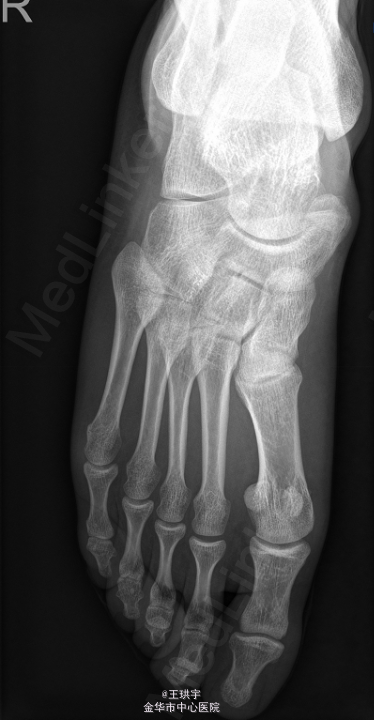

右足副舟骨畸形

后天性扁平足

患者,男,26岁,因“右足部外伤后疼7余年,加重6月 ”入院。

右踝及足背肿胀不明显,右足副舟骨可见明显红肿,皮温正常,足趾活动无殊,末梢循环感觉正常。余肢体无殊。外院 X片示副舟骨畸形.

初步诊断:右足副舟骨畸形,后天性扁平足.在全麻下行“右跟骨截骨内移+副舟骨切除+舟骨切复内固定术+石膏固定术”.